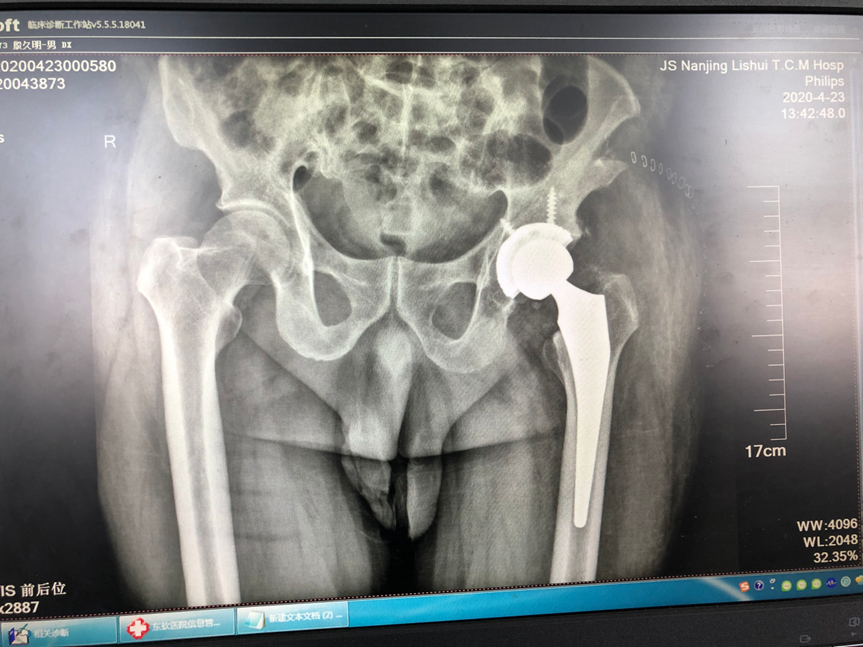

中西医结合治疗骨折是本科的特色;除了运用最先进的手术技术,科室还开展最传统的手法复位小夹板外固定技术,配合自行研发的中药外敷,给患者更好、更多的选择。小夹板固定和骨折微创技术治疗四肢骨折,疗效好,恢复快,效果达到国内先进水平。